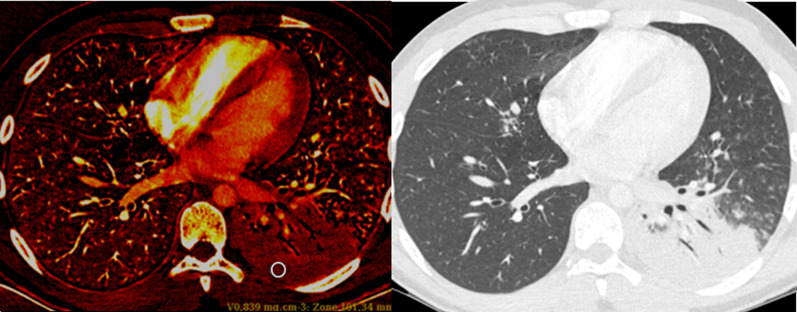

Fig. 3:

19-year-old male with hemoptysis and chest pain. A homogeneous perfusion defect (PD +) is seen (iodine map, left) matching a left basal consolidation (conventional lung images, right). Tuberculous pneumonia was confirmed by PCR assay performed a on sputum sample. Iodine concentration was measured at 0.839 mg/cm3 within the circle and at 0.686 mg/cm3 within the normal-appearing parenchyma